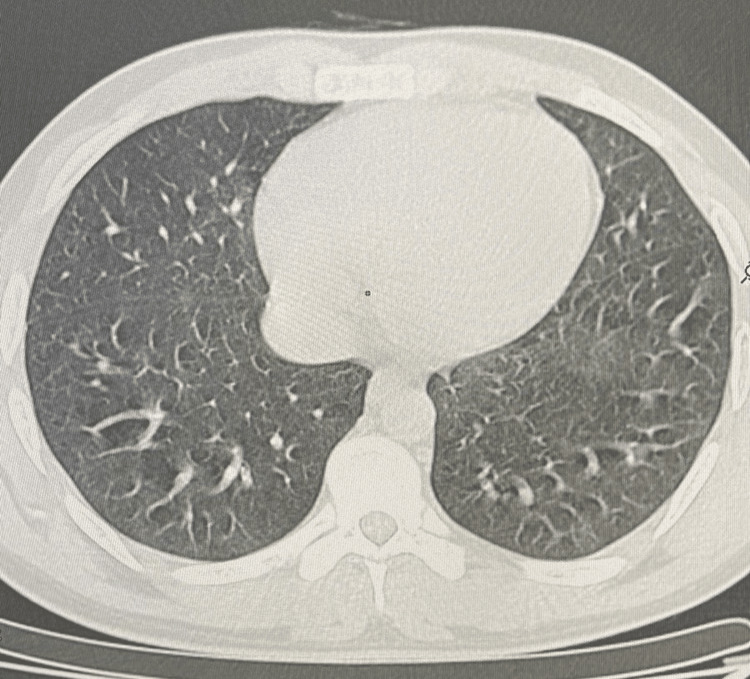

Similar imaging and pathologic findings have been described in patients with smoke synthetic cannabinoids. Over the next week, the patient’s condition improved gradually with supportive care and corticosteroid therapy. He was discharged with a tapering course of oral corticosteroids and close outpatient follow-up. The evolution was marked by clinical, biological and radiological improvement after two months of corticosteroid therapy (Figure 4).